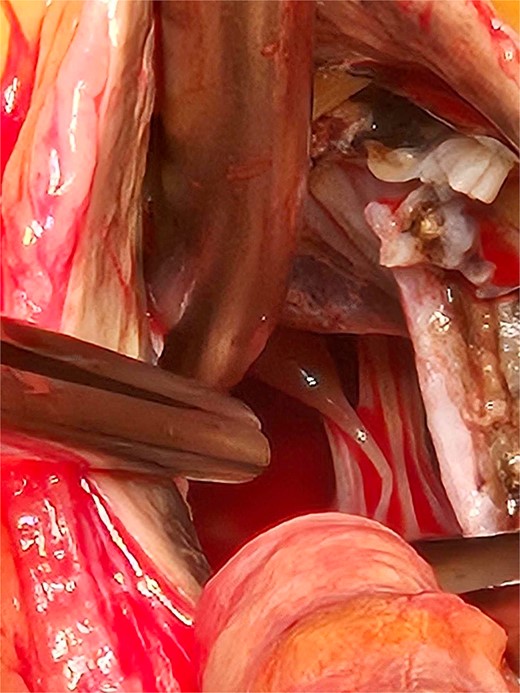

Based on these findings, the patient underwent surgical aortic biological valve replacement and coronary artery bypass grafting (CABG) using a left internal mammary artery graft to the LAD. Intraoperatively, unexpected ochronotic pigmentation was observed in the aortic and mitral valve leaflets, papillary muscles, and the intimal layer of the aortic root, presenting as patchy black discoloration (Figs 1–3). Subsequent biochemical analysis confirmed elevated homogentisic acid levels in the urine, consistent with alkaptonuria.

The patchy ochronotic discolouration can be visualized along the aortic root walls and extending below towards the mitral valve.